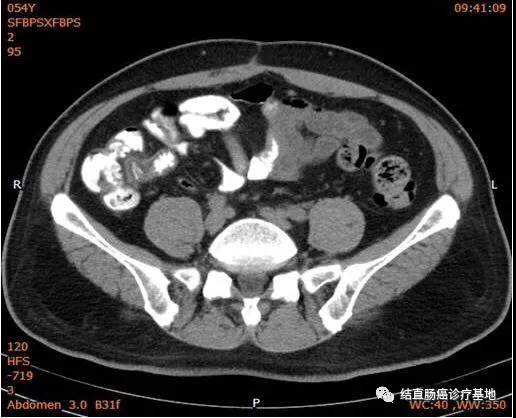

2017年1月16日~2019年9月30日,患者接受CRS+直肠癌根治术+术中IPC+全身系统治疗+间歇维持治疗达到了NED目标(CT图片)